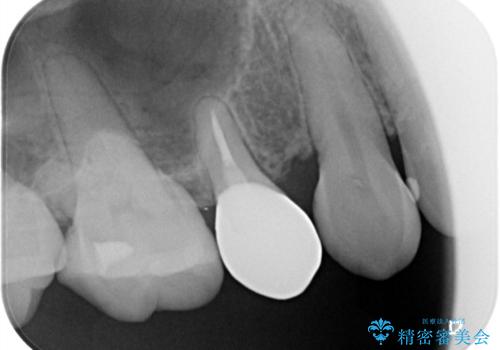

- 元々入っていたセラミックインレーは、6番目と7番目の歯の隙間を無理やり咬合面の近遠心的幅径を伸ばし埋めたような形態で、下部鼓形空隙が広めで食渣が溜まりやすい状態でした。

セラミックインレーを除去したところ、残存歯質が少なく破折のリスクを説明し、オールセラミッククラウン(スタンダード)でのやり替えとなりました。